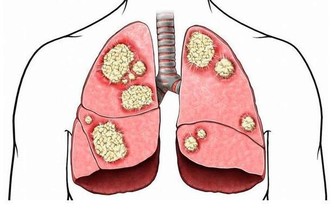

「扁 桃體結石引起的口臭並不少見,大人小孩都可能會出現」,北京中醫醫院耳鼻喉科副主任醫師姜志輝解釋。 扁桃體是人體的免疫器官,位於口咽側壁,包含有 很多隱窩,其中位於扁桃體上極的上隱窩就容易出現結石。 正常情況下扁桃腺隱窩沒有分泌物。 當扁桃體出現急慢性炎症時,就會有脫落上皮、大量淋巴細胞, 白細胞、以及各種致病菌自隱窩排出,若隱窩口堵塞而引起分泌物堆積,時間長了還會導致一些鎂、鈣等無機鹽沉積而引起結石。 這些腐敗的分泌物就會引起口 臭。

另 外,蔡立泰醫師也表示,扁桃腺結石通常看起來像白色或微黃色的小石頭,有時候吐出來時,可以把這些小石頭壓碎,並出現臭臭的味道。扁桃腺結石目前 大多認為是由食物的殘渣及壞菌卡在扁桃腺表面的隱窩中所形成。有些人會感覺到喉嚨卡卡的感覺,嚴重的患者更可能出現頭痛、咽喉疼痛、吞嚥困難、耳朵痛癢、 甚至嘔吐等情形。也因為這些細菌和食物的殘渣以及部分壞死組織的鈣化,所以可能在講話時散發出一些腐爛的臭味,也就是我們所謂的口臭。